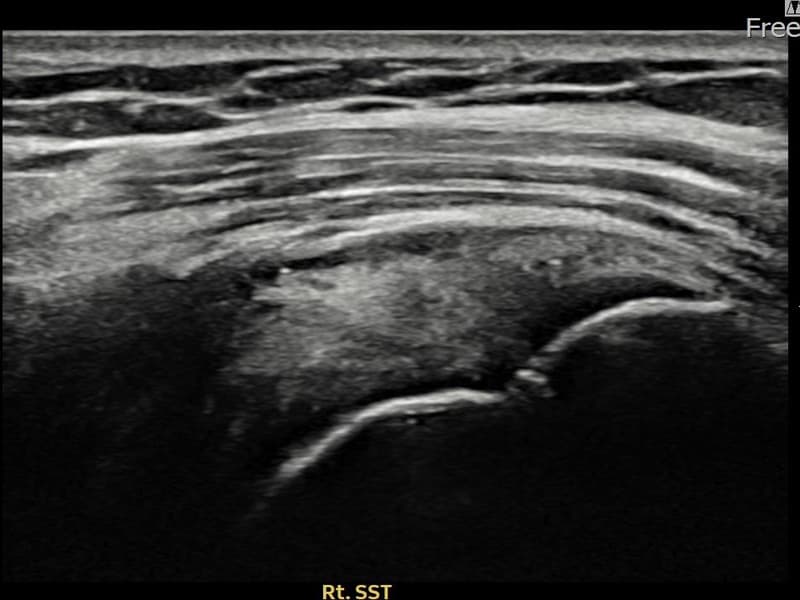

After

시술 전 초음파 측정 결과 파열 크기는 8mm × 4mm (힘줄 두께의 약 35% 결손)로 확인되었습니다. 시술 전 초음파에서 우측 극상근건 점액낭면측의 에코 단절과 힘줄 내 결손 소견이 확인되었습니다. 시술 후 초음파에서 결손 부위에 재생 조직이 채워지고 힘줄 두께가 정상 범위로 회복된 것이 관찰되었습니다.

60대 초반 여성 환자분으로, 우측 어깨 외측 통증이 지속되어 내원하셨습니다. 팔을 머리 위로 올리거나 뒤로 젖히는 동작이 불편하고, 팔꿈치를 붙인 채 팔을 바깥쪽으로 돌릴 때 통증이 심하다고 하셨습니다. 정밀 초음파 검사에서 우측 극상근건 점액낭면측 부분파열이 확인되었으며, 초음파 유도 하 축소봉합술을 시행하였습니다. 시술 후 보조기를 착용하며 재활 운동을 단계적으로 진행하였고, 시술 11주 후 추적 초음파에서 파열 부위 연속성이 회복되어 정상 생활에 복귀하셨습니다.